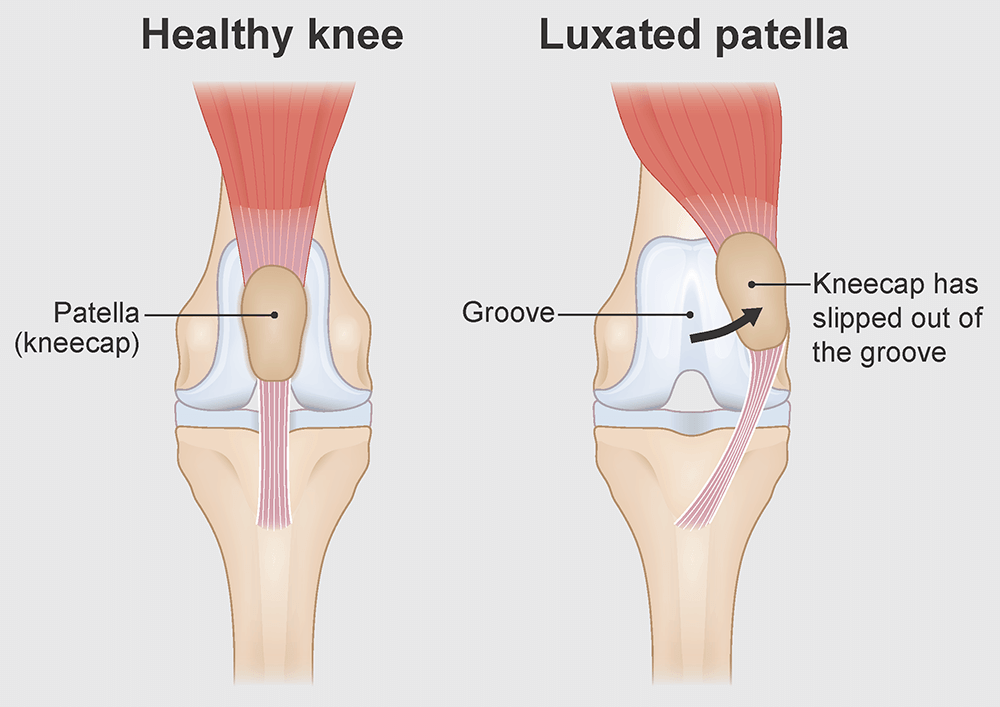

Pros And Cons Of Luxating Patella Surgery. The hospital will give you individualized recovery instructions. As the patella moves in and out of the groove it can wear holes in the cartilage of the patella itself and in the ridge that it rides over when it luxates. Leave a Comment Uncategorized. This causes pain and triggers a cascade of progressive osteoarthritis.

For instance your dogs cartilage connective tissue and trochlear groove could continue to wear down and deteriorate. However his enthusiasm and love for life overrides any pain or discomfort he feels a problem I know all to well from. Recovery From Luxating Patella Surgery. Most of these second surgeries are done because of knee pain. If your dog is not limping frequently and not having her quality of life compromised then a surgery is probably not necessary. As the puppies get bigger the structure can change enough to keep that kneecap in pace.

Leave a Comment Uncategorized. Risks of delaying luxating patella surgery. When your dog has luxating patella the soft tissues on either side of the patella are often too tight or too loose. A grade 2 means the dog can pop them back in themselves. Tightening it helps to prevent the patella from luxating again.

Latte had luxating patella on both her hind knees but only had surgery on one. A luxating patella because the kneecap patella moves out of its usual spot and that causes the dog to suffer unnecessary pain. Recovery From Luxating Patella Surgery. All a luxating patella is is a kneecap that slides in appropriately. Plastic surgery has become increasingly popular over the past decades.

We had lots of pain meds and some to help him settle too. The Timeline for Luxating Patella Surgery Dog Recovery Straight after surgery the majority of Pomeranians will visibly show they feel a degree of tenderness and will limit their range of movement as much as they can. However its best to seek a few vets opinions before you decide. 3 The capsule around the joint is tightened. But if the groove is abnormally shallow or if an injury has damaged the joint the patella can move out of the groove causing the leg to lock up until the kneecap returns to its normal position.